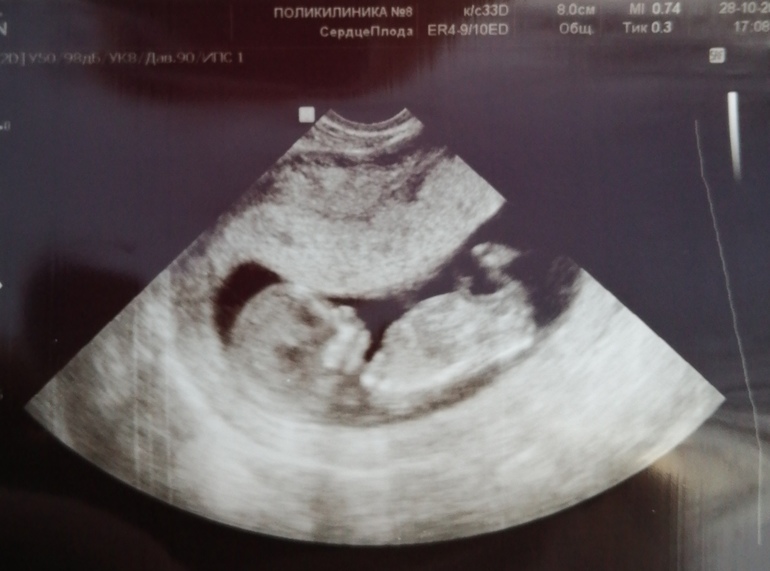

Смотрит моя Г в экран и говорит : " Неужели МаЛЬЧИк?!?!?"😳 Мальчик?🤗 А вы кого хотите?!?!.... Ну нам, конечно, лишь бы здоровенький, но я , если честно имея девочку хотела бы еще девочку, а может это просто из-за отсутствия опыта с мальчиком! Но кто бы там ни был, он естественно самый любимый😍 у моего мужчины свой мальчик и девочка и мою с 2,5 растит, так вот он "чувствует" с самого начала, что там мальчик, говорит 2+2 будет!

Г- :" Не, ну смотрите, тут явно между ног болтается..... нет, ну может, конечно ооооочень большой клитер!"🤣🤣🤣 Причем это "что-то " между ног мы оба тоже увидели. Посмеялись от души. Ну в общем пока такое предположение, естественно , не точное! Вчера вечером показалось, то самое пёрышко щекотящее изнутри, но Г сказал, что еше рано!

А вот и мы